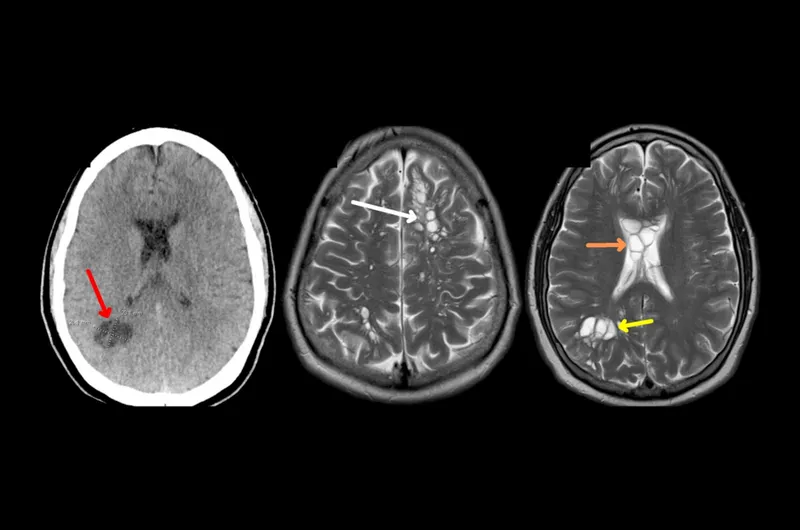

La tomografía practicada al paciente que reveló la causa de la migraña (Imagen: American Journal of Case Reports)

Una tomografía computarizada reveló numerosos focos quísticos, o sea, sacos llenos de líquido en el cerebro. Las pruebas de anticuerpos dieron positivo a quistes de cisticercosis.